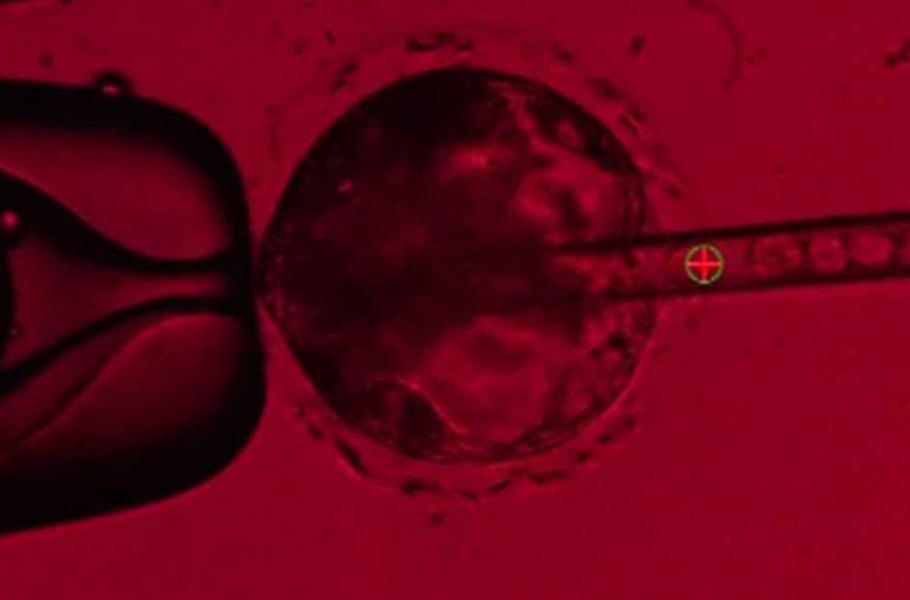

Badatelé se teď snaží pomocí genomového editoru CRISPR upravit geny v prasečím embryu tak, aby se v nich po vložení lidských kmenových buněk mohly vyvíjet lidské orgány. Pokud se jim to povede, tak vytvoří chiméry – stvoření s buňkami ze dvou růžných živočichů, které by mohly zachraňovat lidské životy.

• Pablo Ross / UC Davis